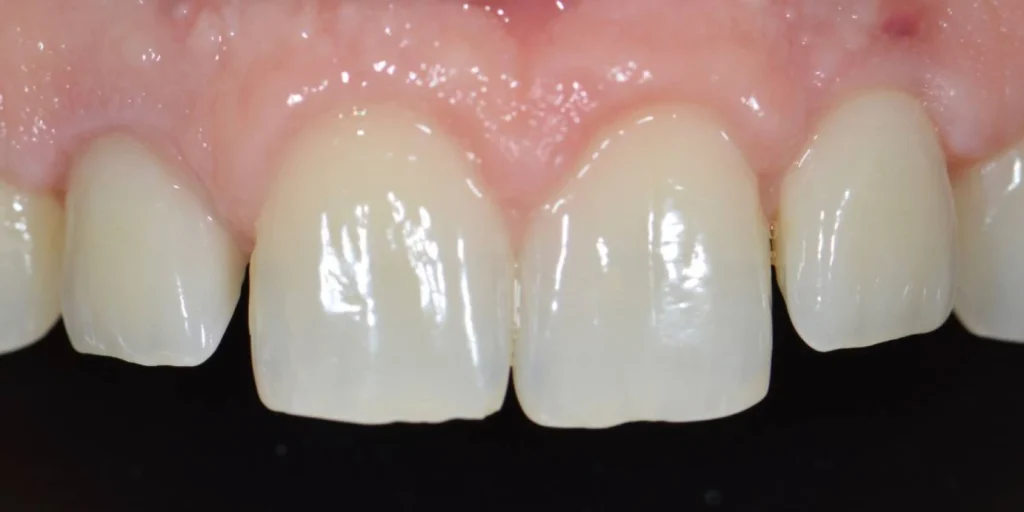

Monsieur R, 33 ans, se présente à la consultation pour améliorer l’esthétique de son sourire. Après une consultation approfondie, nous posons le diagnostic d’une « éruption passive incomplète ». Cela signifie qu’une partie des dents du patient est « cachée » par un excès de gencive. Cela donne l’impression de dents trop petites et d’une gencive trop visible lors du sourire. On appelle cela un « sourire gingival ».

Le traitement va donc consister en une intervention chirurgicale qui permettra de retirer cet excès de gencive pour rendre visible les dents dans leur intégralité. L’intervention réalisée sous anesthésie locale est totalement indolore et les suites opératoires assez limitées. Après quelques jours de cicatrisation, le résultat est déjà présent et le patient ravi d’avoir améliorer l’aspect de son sourire sans avoir touché à ses dents !